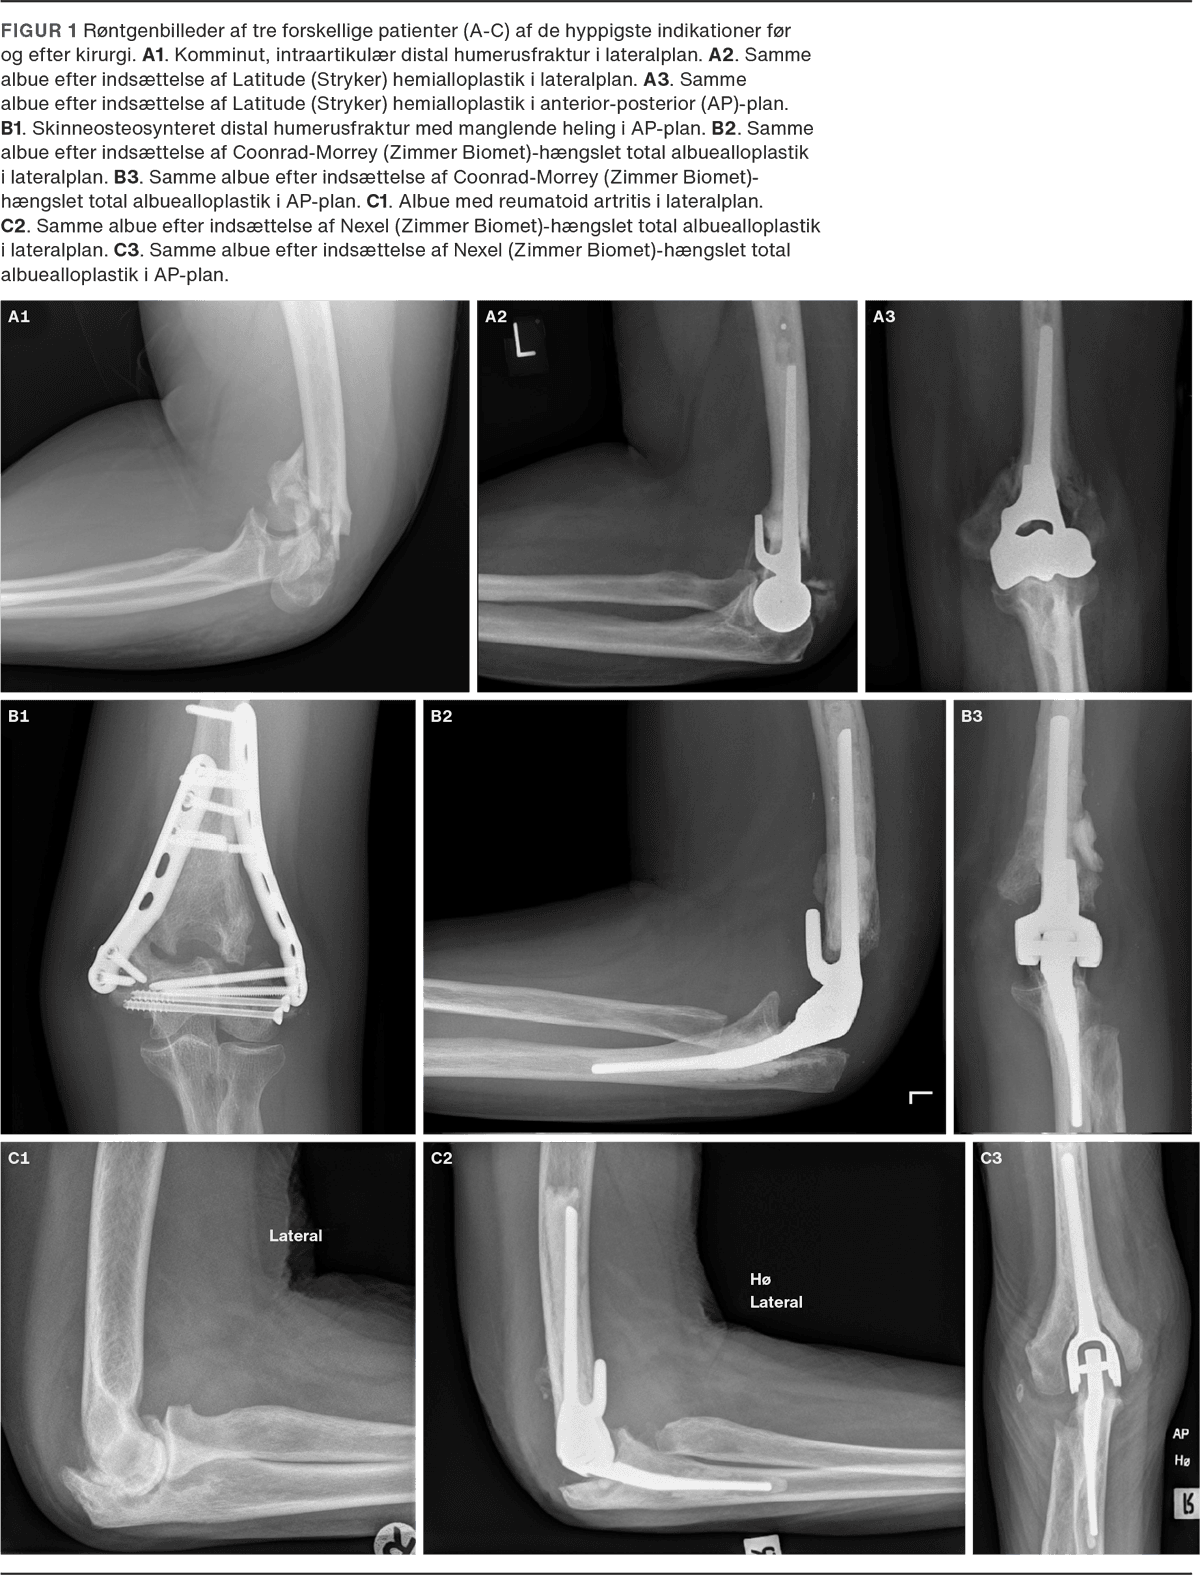

Der foretages ca. 100 albuealloplastikker om året i Danmark, hvoraf omtrent en fjerdedel er revisioner. Albuealloplastikker opdeles i hemialloplastik (EHA), hvor kun distale humerus udskiftes, og total alloplastik (TEA), hvor både proksimale ulna og distale humerus og i sjældne tilfælde caput radii proteseforsynes. TEA kategoriseres yderligere som hængslet eller uhængslet, afhængig af om protesekomponenterne låses sammen eller ej. Den hængslede TEA anvendes hyppigst og på alle indikationer, hvorimod EHA hovedsageligt anvendes til behandling af komminutte distale humerusfrakturer (Figur 1), der ikke kan osteosynteres. På grund af risikoen for løsning af protesekomponenterne tillader hængslet TEA ikke vægtbæring på mere end 5 kg, hvilket er en betydelig begrænsning for mange patienter. Uhængslet TEA er i dag sjælden, men har tidligere været anvendt i behandlingen af patienter med inflammatoriske og degenerative ledsygdomme.

Ved indikation for albuealloplastik på grund af reumatoid artritis anvendes hængslet eller uhængslet TEA. Traditionelt anvendes hængslet TEA i Danmark på grund af ovennævnte komplikationer med uhængslet TEA [6, 19]. Udviklingen af moderne protesedesigns (Figur 2) med større stabilitet har skabt fornyet interesse for uhængslet TEA for patienter med reumatoid artritis, men der mangler fortsat evidens på området.